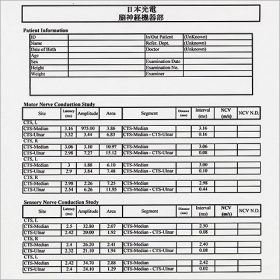

神経伝導検査

しびれ、痛み、麻痺などの神経症状の程度を数値やグラフで客観的に評価します。

得られたデータを実際の症状と比較し、診断の補助や確認を行います。

20~30分ほどで行う検査です。その場で結果の説明をさせて頂きます。

電気刺激を加え、目的とする筋・神経が反応するまでの時間や反応の持続時間、波の高さや波形、左右差などを評価し病変の部位や拡がりを測定します。